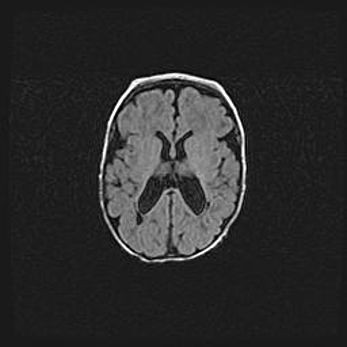

Лейкомаляция с кистозно-глиозной дегенерацией головного мозга.

Возраст: 2 месяца 25 дней

Вес: 6400 г

Окружность головы: 40 см

Срок гестации: 41 неделя

Лейкомаляцию относят к ишемически-гипоксическим повреждениям головного мозга, диагностируемым у новорожденных. При лейкомаляции в головном мозге обнаруживают очаги некроза, возникшие после тяжелой гипоксии и нарушения кровотока. В процессе морфогенеза очаги проходят три стадии: 1) развития некроза, 2) резорбции и 3) формирования глиозного рубца или кисты. Перивентрикулярная лейкомаляция (ПЛ) встречается примерно в 12% случаев среди новорожденных, обычно – у недоношенных детей, причем, частота ее зависит от массы, с которой младенец появился на свет. Наибольшее число малышей страдает лейкомаляцией, если масса при рождении 1500-2500 г.